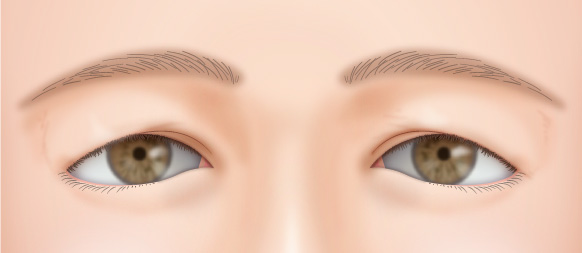

元々まぶたの開きが悪い人は眼瞼下垂手術を併用して目を開けた状態での二重の幅を狭くする修正手術も可能です。

無理に幅広の二重を作った場合、腫れが半年以上も続き、ハム目のようになる場合があります。

前回の手術で皮膚を大きく切除していていなければ幅の狭い二重に修正することが可能です。